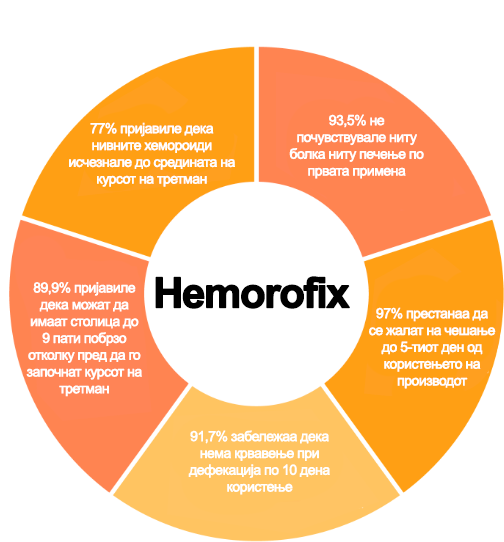

Во 2019 година, беа спроведени независни лабораториски истражувања кои недвосмислено ја потврдија сигурната ефикасност на Хеморофикс. Вкупно 870 доброволци учествуваа во испитувањата. Тие вклучуваа жени и мажи на возраст меѓу 25 и 87 години. Хемороидите на учесниците беа во различни фази. Сите доброволци го тестираа Хеморофикс само 10 дена. Резултатите ги надминаа најлудите очекувања на научниците.

До 98,7% од испитаниците јасно изјавиле дека производот ги елиминира сите симптоми во рок од 48 часа од употребата: болка, печење, чешање, крвавење или неможноста целосно да се испразнат цревата. Истиот број луѓе забележале дека хемороидите не се вратиле по прекинувањето на третманот. По 3 месеци употреба, хемороидите биле трајно елиминирани, дури и во најтешките случаи.

Лабораториските тестови недвосмислено ја докажаа високата ефикасност на производот и елиминирањето на проблемот за само 10 дена. Резултатите исто така покажаа дека кај учесниците во студијата: